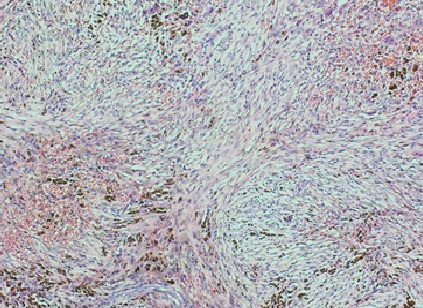

The fracture was first approached via an anterolateral approach to the distal fibula in which the fibula fracture was fixed by a 1/3 tubular plate and screws. This was followed by a complete curettage of the lesion and bone grafting with cancellous bone chips allograft. Finally, the tibia fracture was fixed by minimally invasive percutaneous osteosynthesis (MIPO) technique using 3.5mm locked plate medially (Figure 2). The excised bone material was then sent for histopathological examination which confirmed a non-ossifying fibroma with secondary aneurysmal bone cysts (Figures 3- 5).

Figure 3 Histopathological slide of the lesion-high-power magnification revealing abundant osteophytes and hemosiderin pigmentation.

Figure 4 Histopathological slide of the lesion-high-power magnification showing characteristic spindle cell fibroblastic proliferation consistent with non-ossifying fibroma.

The diagnosis is usually incidental during radiological evaluation for other reasons.4 Due to its characteristic radiological appearance, pathological confirmation is usually not necessary.5,7 This is especially true when the lesion demonstrates characteristic features such as a longitudinal growth pattern, lobulated and bubbly appearance with sclerotic border, and intact cortex.7 If however, any of these features is breached or in complicated cases, biopsy may be indicated.7 Histologically, the lesion reveals storiform fibrous tissue with spindle cells, multinucleated giant cells, hemosiderin and xanthoma cells.8  Secondary aneurysmal bone cysts are usually not present in the primary lesion. The presence of such changes is probably attributed to the complicated pathological fracture which results in bleeding and the formation of blood-filled spaces.7